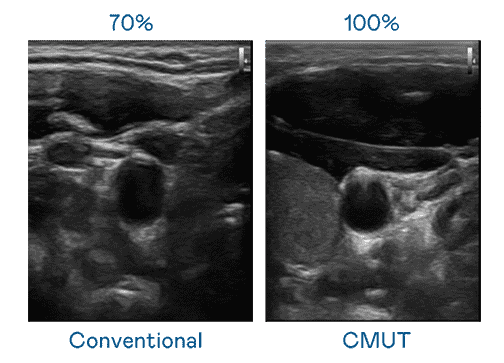

CMUT 技术是一种用电容式微机电元件来产生超音波讯号的技术。。与传统 PZT 压电式技术相比,,,CMUT 频宽增加 30%,,,,更宽频的超音波讯号让影像解析度大幅提升,,是实现高影像品质医疗超音波扫描、、促进精准医疗发展的关键技术。。。

超音波影像的解析度高低,,,首先取决于探头能发出的讯号频宽。。28国际 CMUT 可提供高清晰的超音波讯号,,,,提供高频宽、、、、高灵敏度、、、影像纹理细节更高的超音波影像,,,协助医护人员缩短影像判读时间及利用精准的医疗影像进行诊断。。。。